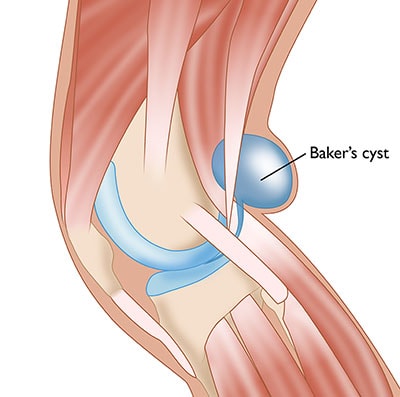

A Baker’s cyst is not a primary pathology — it is a secondary symptom. When the knee joint produces excess synovial fluid (in response to OA, meniscal tears, or RA), the fluid is pushed into the popliteal fossa (back of the knee) through a one-way valve in the joint capsule, forming a cyst. Treating the underlying cause — and aspirating the cyst under ultrasound guidance — resolves the problem definitively.

Caution: A ruptured Baker’s cyst can mimic a deep vein thrombosis (DVT) — causing sudden calf pain and swelling. Both conditions require urgent clinical assessment to distinguish them. IBAP Clinics uses ultrasound imaging to confirm the diagnosis at the point of care.

In most cases, no. A Baker’s cyst (popliteal cyst) is a secondary problem caused by excess fluid in the knee joint — typically from osteoarthritis, a meniscal tear, or inflammatory arthritis. Surgically removing the cyst without treating the underlying cause invariably leads to recurrence. At IBAP Clinics, we first identify and treat the root cause (e.g., PRP or BMAC for OA, HA injection, or anti-inflammatory management for RA). The cyst can then be aspirated under ultrasound guidance and, if necessary, a corticosteroid or hyaluronic acid injection administered. Surgery is very rarely required for an isolated Baker’s cyst.